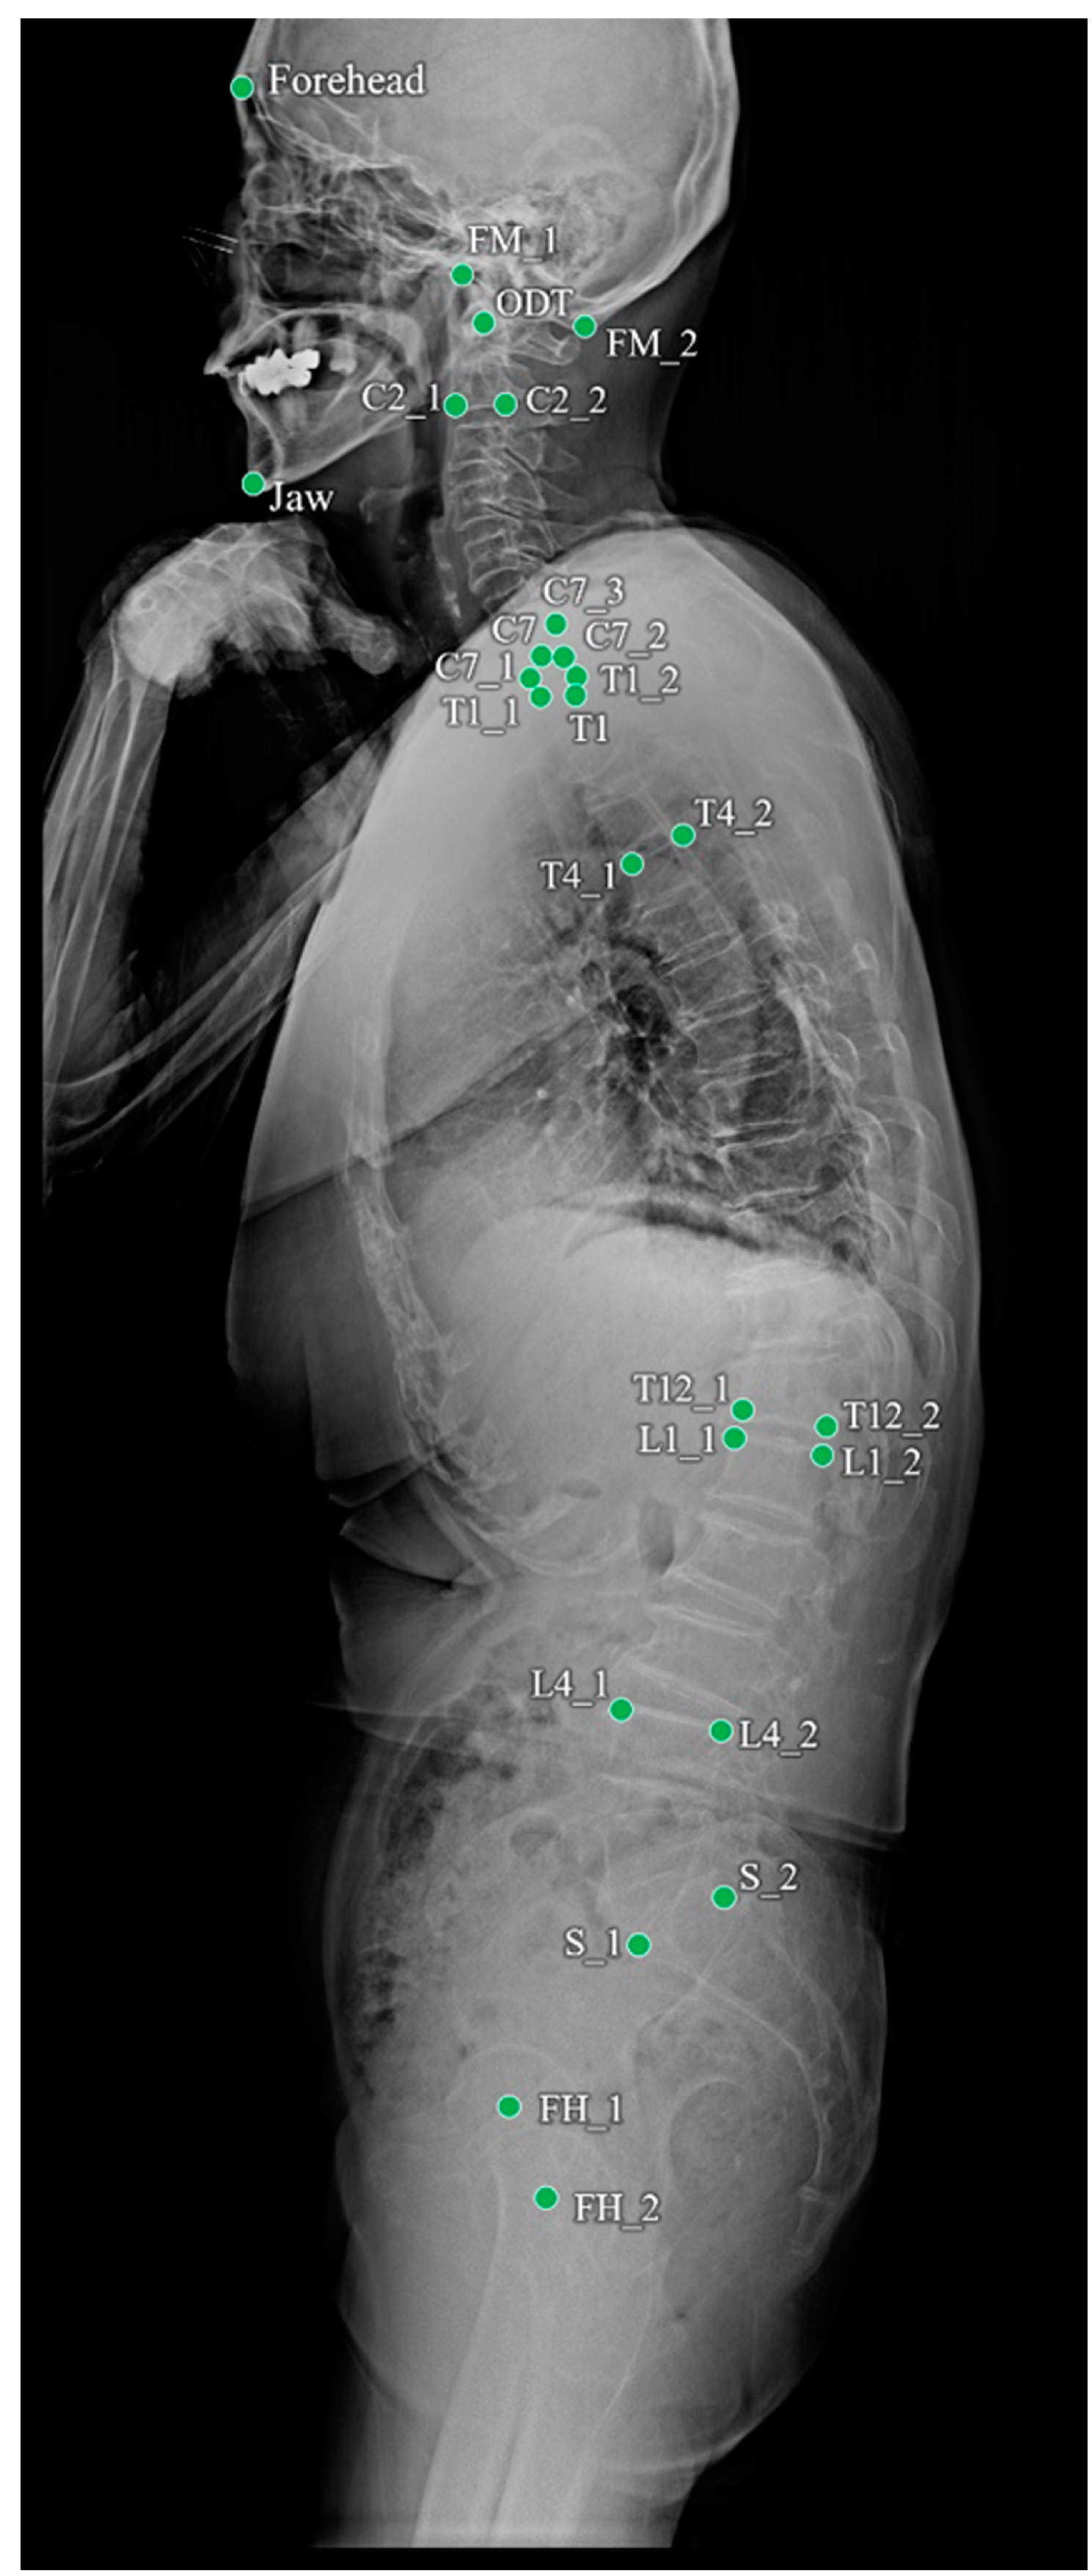

Of the 1017 radiographs, data from 819 and 198 were used for training and testing the performance of the landmark detection model, respectively. To objectively evaluate the performance of the program, 690 whole-spine radiographs from four other institutions were used for external validation. The annotated landmarks contained 26 points, as shown in Table 1 and Figure 1. The demographic profile for these 1707 annotated images revealed a mean patient age of 42.2 ± 27.3 years (age range: 20–85 years) at the time of the radiographic examinations.

Figure 1.

Landmarks annotated on a whole-spine lateral radiograph.